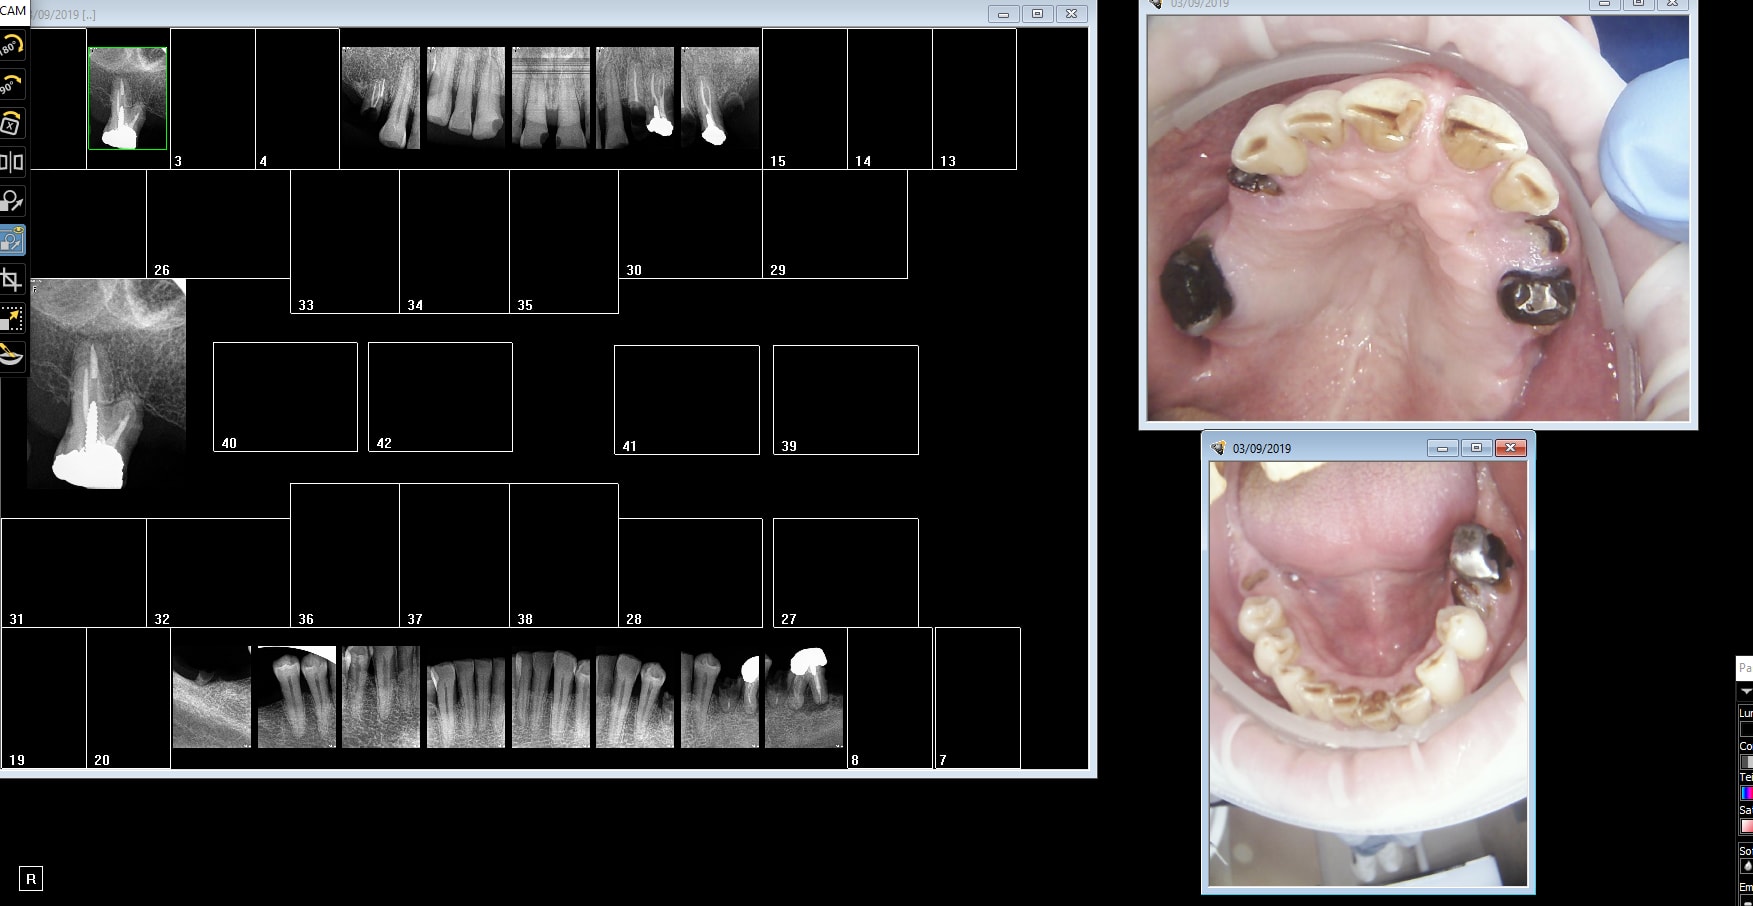

Capture_d_écran_2019-09-05_08.53.43_xrhdot.png

Capture_d_écran_2019-09-04_21.19.10_a55pcs.png